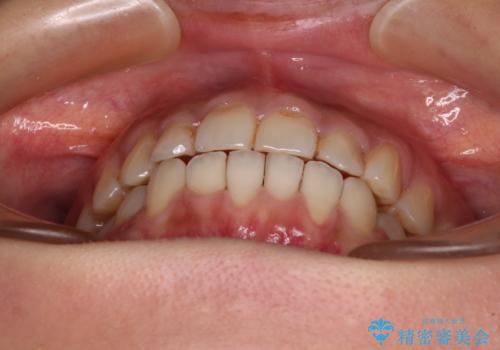

前歯のデコボコとクロスバイト インビザラインによる矯正治療

- 2年8ヶ月

- 上下のクロスバイトと前歯のデコボコを気にして来院された患者様です。

骨格的に下顎がやや前方にあり、奥歯にクラウンが装着されているため、矯正治療後半の不安定な咬み合わせを避けるのであればワイヤー矯正がおすすめとなりますが、希望によりインビザラインにて治療を行うこととしました。

インビザラインを用い、IPR(歯と歯の間を削る)と歯列全体を拡大させることで、歯並びを整えていくこととしました。

懸念されたとおり、右下のクラウン部分が全く咬み合わず、仕上げの段階で治療期間が長くなりました。